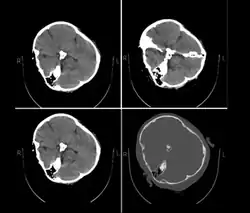

On 16 September 2022, 22-year-old Kurdish-Iranian woman Mahsa Amini,[a] also known as Jina Amini,[b][1][2][3] died in a hospital in Tehran, Iran, under suspicious circumstances. The Guidance Patrol, the religious morality police of Iran's government, had arrested Amini for allegedly not wearing the hijab in accordance with government standards. The Law Enforcement Command of the Islamic Republic of Iran stated that she had a heart attack at a police station, collapsed, and fell into a coma before being transferred to a hospital.[4][5] However, eyewitnesses, including women who were detained with Amini, reported that she was severely beaten and that she died as a result of police brutality,[6][7][8] which was denied by the Iranian authorities.[9] The assertions of police brutality, in addition to leaked medical scans,[10] led some observers to believe Amini had a cerebral hemorrhage or stroke due to head injuries received after her arrest.[11]

Published hospital pictures show Mahsa Amini bleeding from the ear and with bruises under her eyes. In an 18 September letter, Doctor Hossein Karampour (the top medical official in Hormozgan province), pointed out that such symptoms "do not match the reasons given by some authorities who declared the cause to be a heart attack... (they are instead consistent with) a head injury and the resulting bleeding."[76] This was also confirmed by alleged medical scans of her skull, leaked by hacktivists, showing bone fracture, hemorrhage, and brain edema.[10][77]

By 21 September, the hospital had released preliminary CT scans. Government supporters stated the CT scans showed psychological stress caused by a previous brain operation; critics stated the scans showed physical beating and trauma. The Iranian government stated Amini had a brain operation at the age of five.[81]